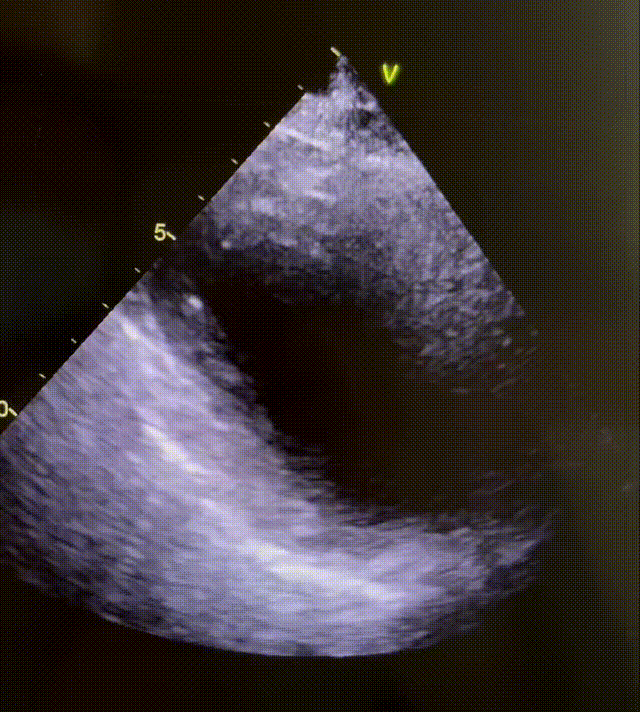

当然如果要做心脏彩超去证实,一定要找有丰富经验和手法好的心超医生,因为心尖部不好打,心尖部的疾病最容易漏诊,包括心尖部肥厚型心肌病、应激性心肌病。

感谢我们医院心超室的叶医生每次都能打出漂亮的心尖球囊样改变的超声动图(即传说中北海道的“章鱼壶”样),让每例应激性心肌病都有一个完美的闭环。

第2例:2025.9.22呼吸科会诊的病例。发现会诊的病例当中,呼吸科的应激性心肌病是最多的,特别是慢性阻塞性肺疾病、支气管哮喘、肺部感染这些躯体疾病最容易诱发。78岁的女性,肺癌,这次是肺部感染诱发。